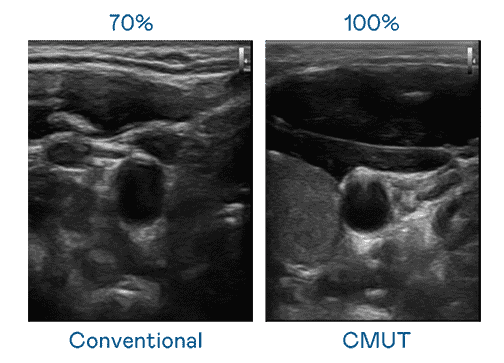

CMUT 技术是一种用电容式微机电元件来产生超音波讯号的技术。。。与传统 PZT 压电式技术相比,,CMUT 频宽增加 30%,,更宽频的超音波讯号让影像解析度大幅提升,,,,是实现高影像品质医疗超音波扫描、、、促进精准医疗发展的关键技术。。

大频宽带来超清晰影像

超音波影像的解析度高低,,,首先取决于探头能发出的讯号频宽。。。尊时凯龙 CMUT 可提供高清晰的超音波讯号,,,提供高频宽、、、高灵敏度、、影像纹理细节更高的超音波影像,,协助医护人员缩短影像判读时间及利用精准的医疗影像进行诊断。。。。